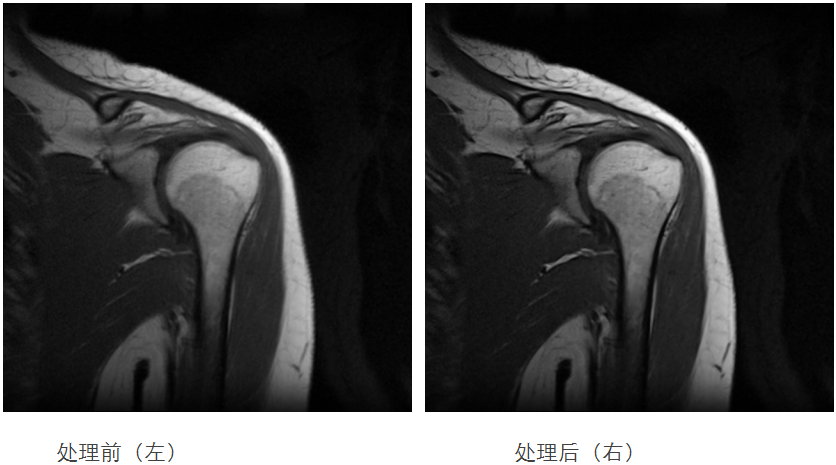

康泰瑞影携新一代医学影像创新技术亮相2025